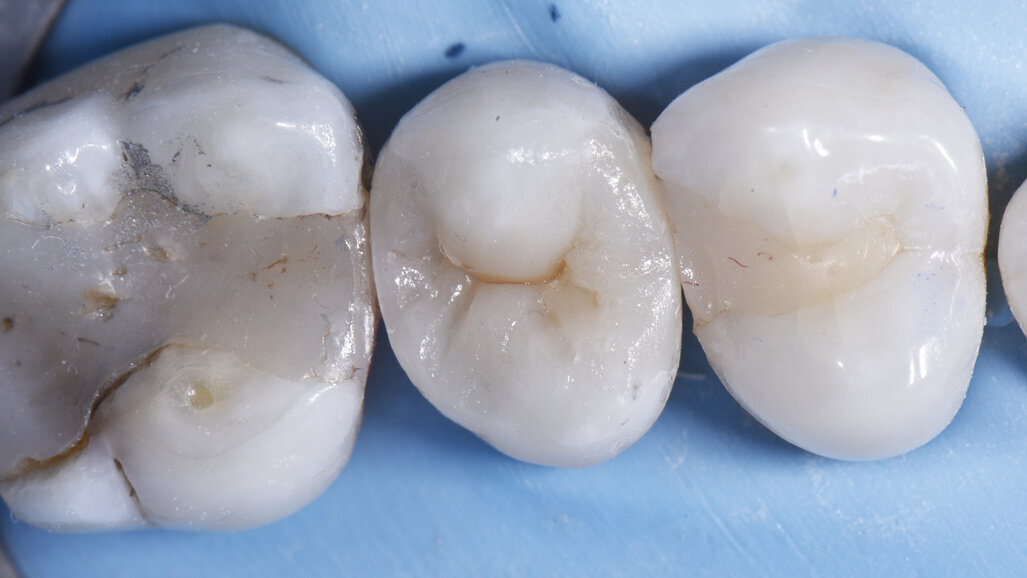

After - Final result after placement of lingual lobe and characterisation. This result demonstrates the superb handling, sculptability and chameleon effect of the universal, cloud-shaded ceram.x® SphereTEC™ one composite featuring spherical fillers for ultimate control of placement. Note the precision of line angle and bucco-lingual embrasure formation with Palodent® V3.

The body composite chosen, Dentsply Sirona’s ceram.x® SphereTEC™ one, features SphereTEC™ technology using spray granulation to produce spheres with a mean size of 15 µm out of primary submicron filler glass. These spheres minimise frictional forces when under stress. On the other side, the irregularly shaped primary particles ensure high slump resistance, thus leading to excellent sculptability. The Cloud Shading Concept adopted by Dentsply Sirona’s ceram.x® SphereTEC™ one allows a single shade to umbrella a cluster of shades, by its distinct chameleon effect, permitting a minimalised armamentarium.

All in all, the Class II Solution™ offered by Dentsply Sirona is elegant, efficient and precise; three features I strive to achieve in every restoration.